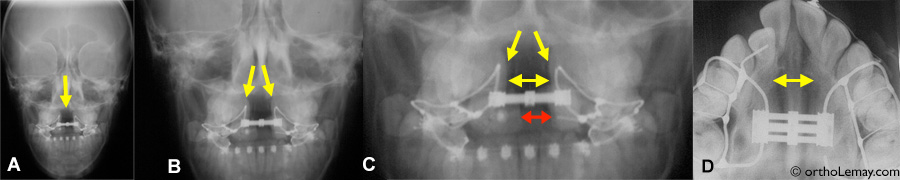

Vue de face (antéro-postérieure), une radiographie montre clairement l’ouverture au niveau de la suture palatine indiquée par les flèches jaunes.

A, B et C représentent la même radiographie agrandie. On y voit aussi la vis d’expansion qui a atteint son ouverture maximale.

La flèche rouge en (C) indique l’ouverture entre les incisives centrales.

(D) Radiographie occlusale où l’ouverture de la suture est clairement visible. Les régions plus foncées sur les radiographies sont l’endroit où les os du maxillaire se sont séparés.